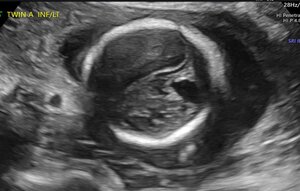

At 20w0d gestation, the patient returned for a repeat ultrasound study which showed a left cerebral mass with a dysplastic appearance, and evident mass effect on the ipsilateral ventricle (Figure 3). The expanded differential at that time included a fetal brain mass, with the highest suspicion for a teratoma. Less likely etiologies included a malformation secondary to a cerebral vascular accident and a congenital brain malformation. As no in utero interventions were indicated based on the suspected diagnosis, focus was directed toward confirming the presence of a fetal brain tumor. Relative growth of this suspected mass over time, measured by a repeat fetal MRI, was possibly suggestive of an aggressive fetal neoplasm.